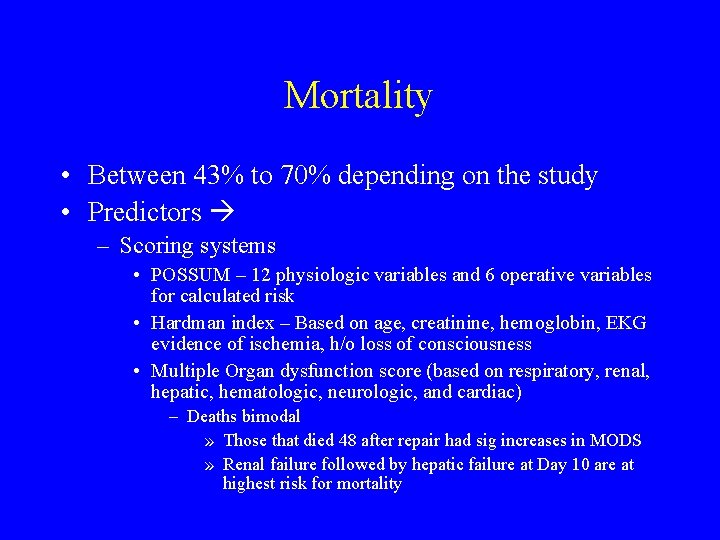

Mortality • Between 43% to 70% depending on the study • Predictors – Scoring systems • POSSUM – 12 physiologic variables and 6 operative variables for calculated risk • Hardman index – Based on age, creatinine, hemoglobin, EKG evidence of ischemia, h/o loss of consciousness • Multiple Organ dysfunction score (based on respiratory, renal, hepatic, hematologic, neurologic, and cardiac) – Deaths bimodal » Those that died 48 after repair had sig increases in MODS » Renal failure followed by hepatic failure at Day 10 are at highest risk for mortality